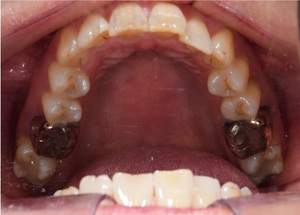

矯正中

【担当医師所見】

左右上下合わせて4本の抜歯を行った

①前歯もキレイに並んできました

②上の歯が外側になり、交叉咬合がなくなりました

③左上の出ていた歯を元の位置までもどしています